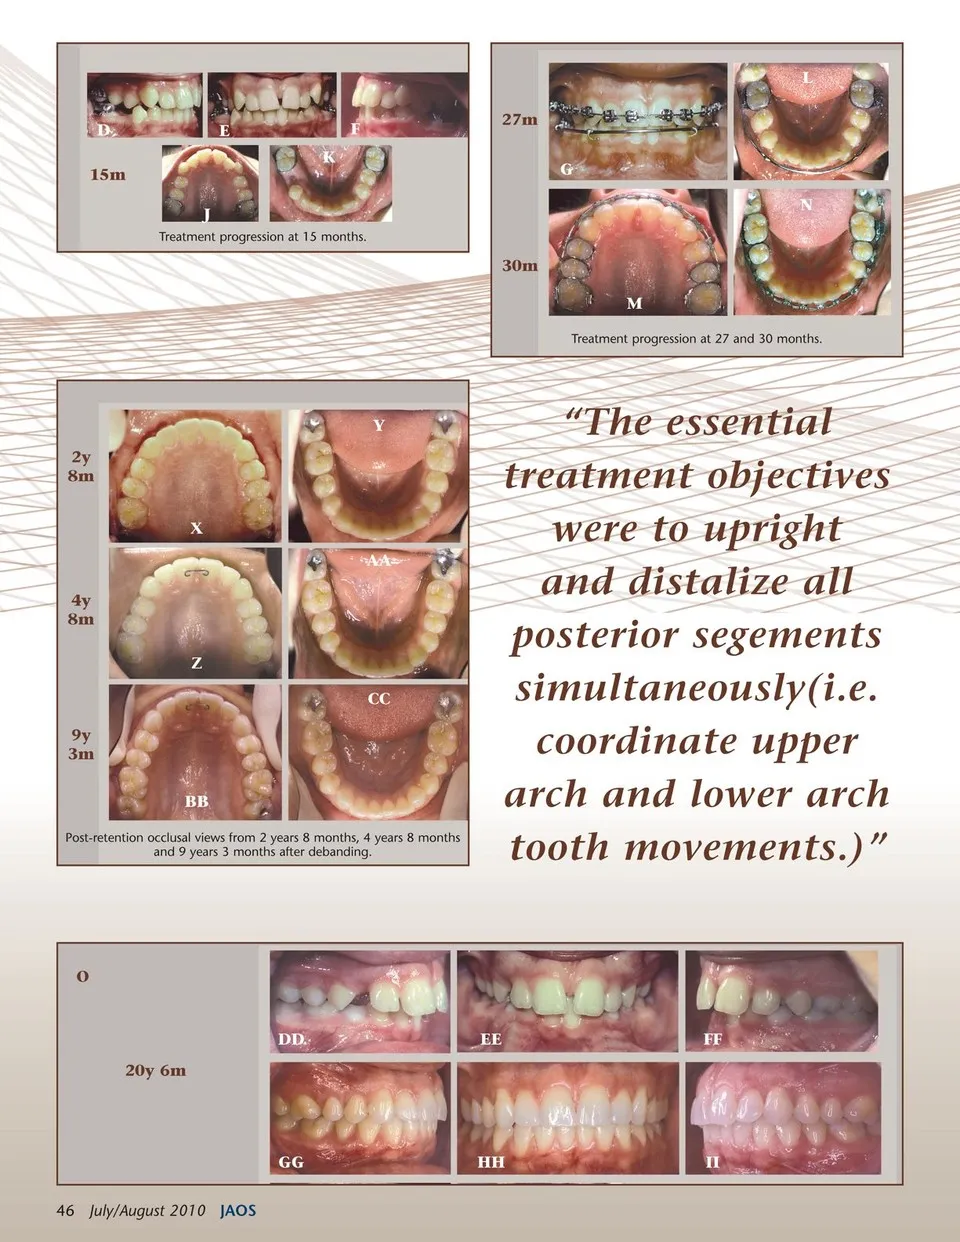

L D 15m J Treatment progression at 15 months. 30m M Treatment progression at 27 and 30 months. E K F 27m G N Y 2y 8m X AA 4y 8m Z CC 9y 3m BB Post-retention occlusal views from 2 years 8 months, 4 years 8 months and 9 years 3 months after debanding. “The essential treatment objectives were to upright and distalize all posterior segements simultaneously(i.e. coordinate upper arch and lower arch tooth movements.)” O DD 20y 6m EE FF GG 46 July/August 2010 JAOS HH II